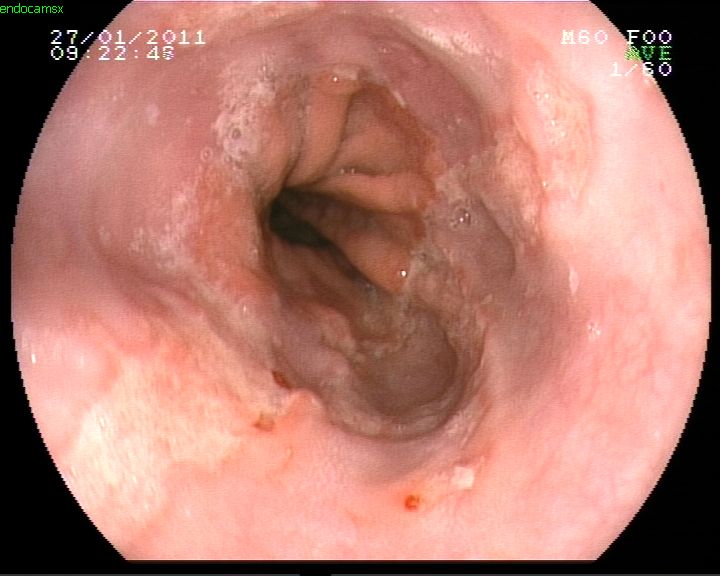

Reflüye bağlı yemek borusu ülserleri